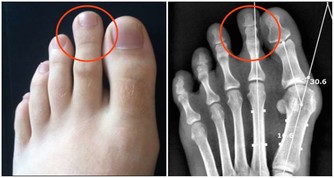

初次就診時,小董不僅黑眼圈嚴重,精神不振,還有易疲勞、睡覺打呼嚕等症狀。

小孩擠眉弄眼,有黑眼圈家長要引起重視

小朋友因為好動,日常會有很多小動作,很多家長會不以為然,但如果發現寶寶長期以往臉部有奇怪的表情,那就要引起注意了,寶寶很可能是患上過敏性鼻炎了。

2.黑眼圈大而重